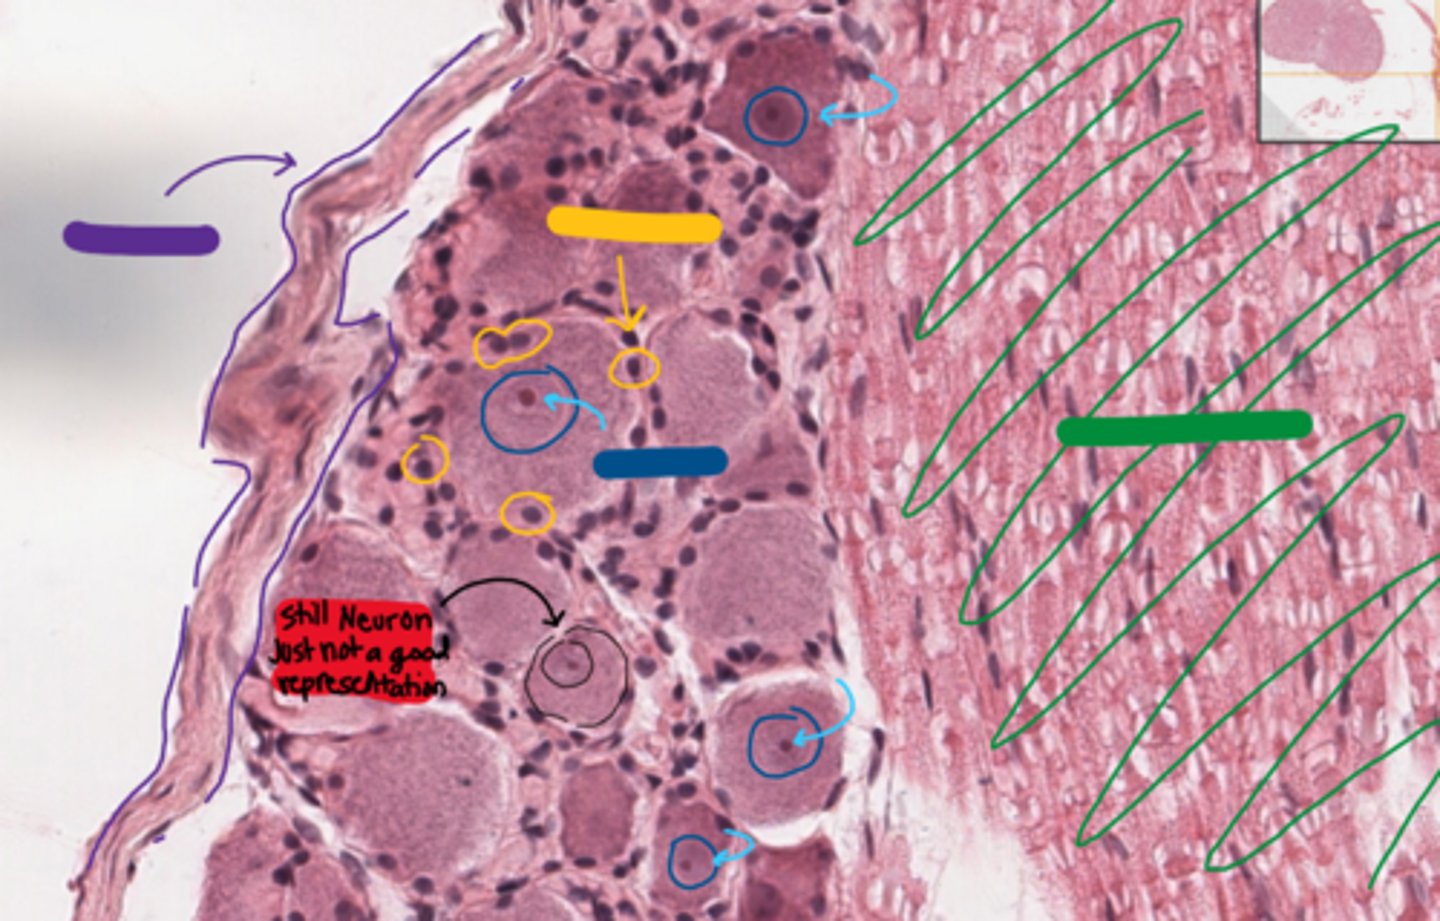

This is blurry but its a dorsal root ganglion I swear.

What tends to be peripherally located in the red areas?

axons

What tends to be centrally located in the green areas?

cell bodies

red

satellite cells

blue

epineurium

purple

neurons

green

epineurium/perineurium

yellow

axon region

nucleus is NOT centrally located

the neuron indicated in red.

Why is it not a good representation of a dorsal root ganglion neuron?

RER

what organelle is the nissl substance in these neurons made of?